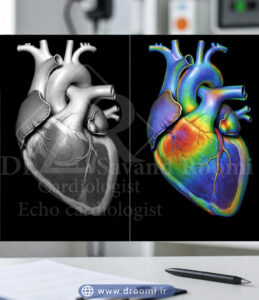

در تصاویر اکو داپلر رنگی، جریان خون به سمت پروب (دستگاه) معمولاً با رنگ قرمز و جریان دور شونده با رنگ آبی نشان داده میشود. اگر جریان خون آشفته (توربولنت) باشد، رنگ سبز یا زرد اضافه میشود تا ناهنجاریها مانند نشت دریچه یا تنگی عروق برجسته شوند.

تصویر آموزشی که پیشرفت اکو داپلر رنگی قلب را با ترکیب تصویر دوبعدی و جریان خون رنگی نمایش میدهد.

اکوکاردیوگرافی داپلر رنگی از دهه ۱۹۸۰ میلادی به عنوان یک انقلاب در تصویربرداری قلب معرفی شد و امروزه یکی از پرکاربردترین ابزارهای تشخیصی در کاردیولوژی است. این روش با ترکیب تصویر دوبعدی سیاهوسفید قلب و لایه رنگی جریان خون، امکان مشاهده همزمان ساختار و عملکرد دینامیک قلب را فراهم میکند.

این تصویر تفاوت اصلی اکو داپلر رنگی و اکو قلب معمولی را با نمایش لایه رنگی جریان خون نشان میدهد.

تکنیک داپلر رنگی یک لایه پیشرفته به اکوکاردیوگرافی پایه اضافه میکند و نه تنها ساختار قلب را نشان میدهد، بلکه جریان خون را به صورت رنگی و واقعی نمایش میدهد. این فناوری بر پایه اصل فیزیکی اثر داپلر کار میکند و تفاوت اصلی اکو رنگی با اکو معمولی را تشکیل میدهد.

تبدیل دادههای سرعت به رنگ (قرمز برای جریان به سمت پروب، آبی برای دور شدن)

در اکوکاردیوگرافی داپلر رنگی، دادههای سرعت و جهت به رنگ تبدیل میشوند و روی تصاویر دوبعدی سیاهوسفید superimpose (همپوشانی) میگردند. به طور استاندارد:

– جریان خون به سمت پروب (نزدیک شدن) با رنگ قرمز نشان داده میشود.

– جریان خون دور شونده از پروب با رنگ آبی نمایش داده میشود.

شدت رنگ (روشنتر یا تیرهتر) نشاندهنده سرعت بالاتر یا پایینتر است. این کد رنگی (معروف به BART: Blue Away, Red Toward) به پزشکان کمک میکند تا جهت طبیعی یا غیرطبیعی جریان را سریع تشخیص دهند.